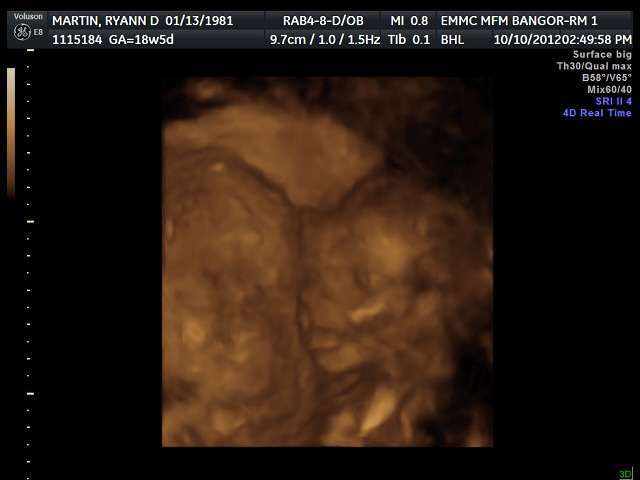

During our BPP our son had lots of questions for the ultrasound tech. I love our doctor's office and I love the ultrasound clinic just as much. The wonderful tech was so good about answering every question he had and even giving him a snack and a drink when he said his tummy hurt from being hungry. We were there for well over an hour as the tech took her time explaining to our son what she was looking for. After her amniotic fluid was measured, her practice breathing assessed and her growth measurements taken, the tech spent quite a bit of time just playing around with our baby girl. We were able to watch as she waved, smiled and even opened her eyes to look around. It was by far the most amazing ultrasound I have every experienced and would love to share some photos of that day with you. So here is our baby girl, who by the way still doesn't have a name. :) I hope this makes up for my lack of posts.

I am so in love with her chubby little cheeks!

And her beautiful little lips.

She looks so much like her big brother!!